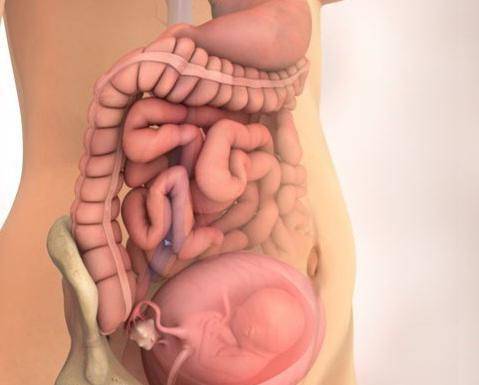

16-17 недель беременности: развитие малыша